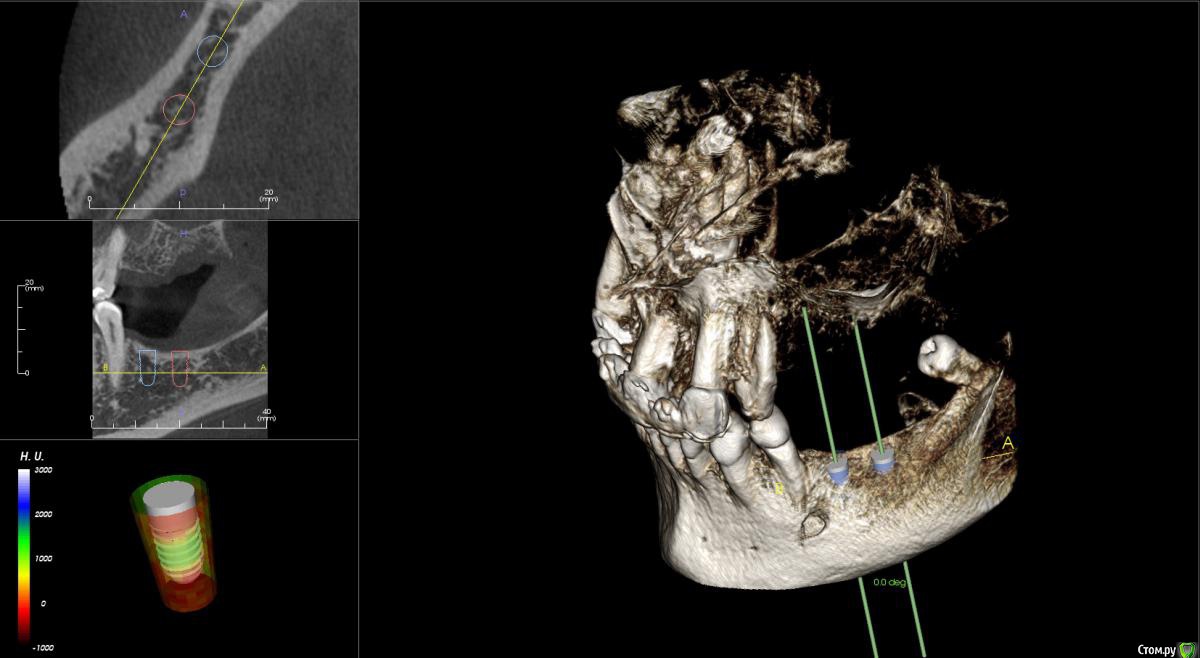

kamranchick Опубликовано 17 февраля, 2015 Поделиться Опубликовано 17 февраля, 2015 Добрый вечер.Имеется следующая проблемаПациент обратлся с жалобами в области отсутствия жевательных зубов, планируется имплантация.Вопросы такого плана, в области 3 сегмента думаю сделать расщепление гребня, установка имплантов 3,75/8 и аугментация костью Ostebiol Gen-Os, мембрана.В области 4 сегмента больше сомнения, планируется титановая сетка +аугментация, либо расщепление опять же, планирую разделить восстановление и имплантауию на 2 этапа в 4 сегментеКакие будут комментарии? Ссылка на комментарий

Shuvalov Опубликовано 17 марта, 2015 Поделиться Опубликовано 17 марта, 2015 Добрый вечер.Имеется следующая проблемаПациент обратлся с жалобами в области отсутствия жевательных зубов, планируется имплантация.Вопросы такого плана, в области 3 сегмента думаю сделать расщепление гребня, установка имплантов 3,75/8 и аугментация костью Ostebiol Gen-Os, мембрана.В области 4 сегмента больше сомнения, планируется титановая сетка +аугментация, либо расщепление опять же, планирую разделить восстановление и имплантауию на 2 этапа в 4 сегментеКакие будут комментарии?Думаю Mane прав И получите прогнозируемый результат! Без сетки! Сосиска рулит Ссылка на комментарий